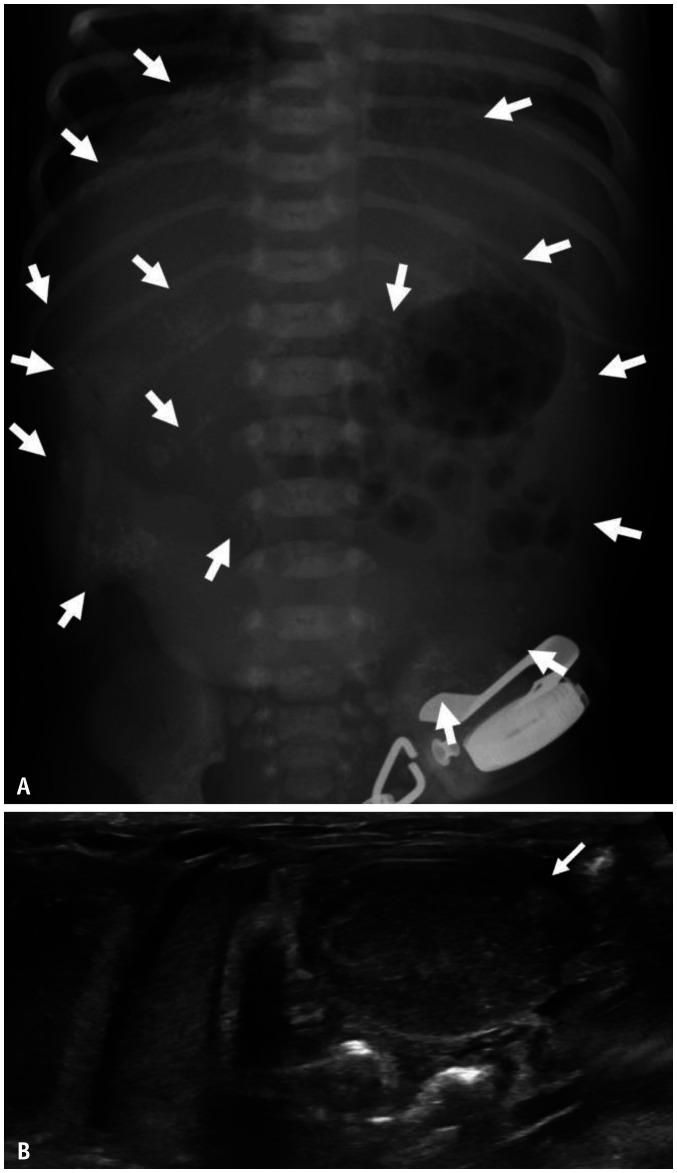

Gastrointestinal (GI) emergencies in neonates and infants encompass from the beginning to the end of the GI tract. Both congenital and acquired conditions can cause various GI emergencies in neonates and infants. Given the overlapping or nonspecific clinical findings of many different neonatal and infantile GI emergencies and the unique characteristics of this age group, appropriate imaging is key to accurate and timely diagnosis while avoiding unnecessary radiation hazard and medical costs. In this paper, we discuss the radiological findings of essential neonatal and infantile GI emergencies, including esophageal atresia and tracheoesophageal fistula, hypertrophic pyloric stenosis, duodenal atresia, malrotation, midgut volvulus for upper GI emergencies, and jejunoileal atresia, meconium ileus, meconium plug syndrome, meconium peritonitis, Hirschsprung disease, anorectal malformation, necrotizing enterocolitis, and intussusception for lower GI emergencies.

新生儿和婴儿的胃肠道(GI)急症涵盖了从胃肠道的开始到结束的各个方面。先天性和后天性疾病都可能导致新生儿和婴儿出现各种胃肠道急症。鉴于许多不同的新生儿和婴儿胃肠道急症的临床发现具有重叠或非特异性,以及该年龄段的独特特征,适当的影像学检查对于准确和及时的诊断至关重要,同时避免不必要的辐射危害和医疗费用。在本文中,我们讨论了基本的新生儿和婴儿胃肠道急症的放射学表现,包括食管闭锁和食管气管瘘、肥厚性幽门狭窄、十二指肠闭锁、肠旋转不良、胃上消化道急症,以及空肠回肠闭锁、胎粪性肠梗阻、胎粪栓综合征、胎粪性腹膜炎、先天性巨结肠、肛门直肠畸形、坏死性小肠结肠炎和肠套叠等下消化道急症。